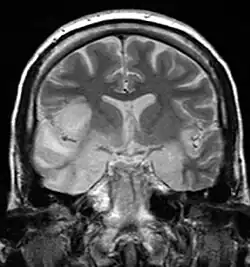

| Herpesviral encephalitis and herpesviral meningitis | Herpes simplex encephalitis (HSE) is a rare life-threatening condition that is thought to be caused by the transmission of HSV-1 either from the nasal cavity to the brain's temporal lobe or from a peripheral site on the face, along the trigeminal nerve axon, to the brainstem.[19][20][21][22] Despite its low incidence, HSE is the most common sporadic fatal encephalitis worldwide. HSV-2 is the most common cause of Mollaret's meningitis, a type of recurrent viral meningitis. | ![]() |